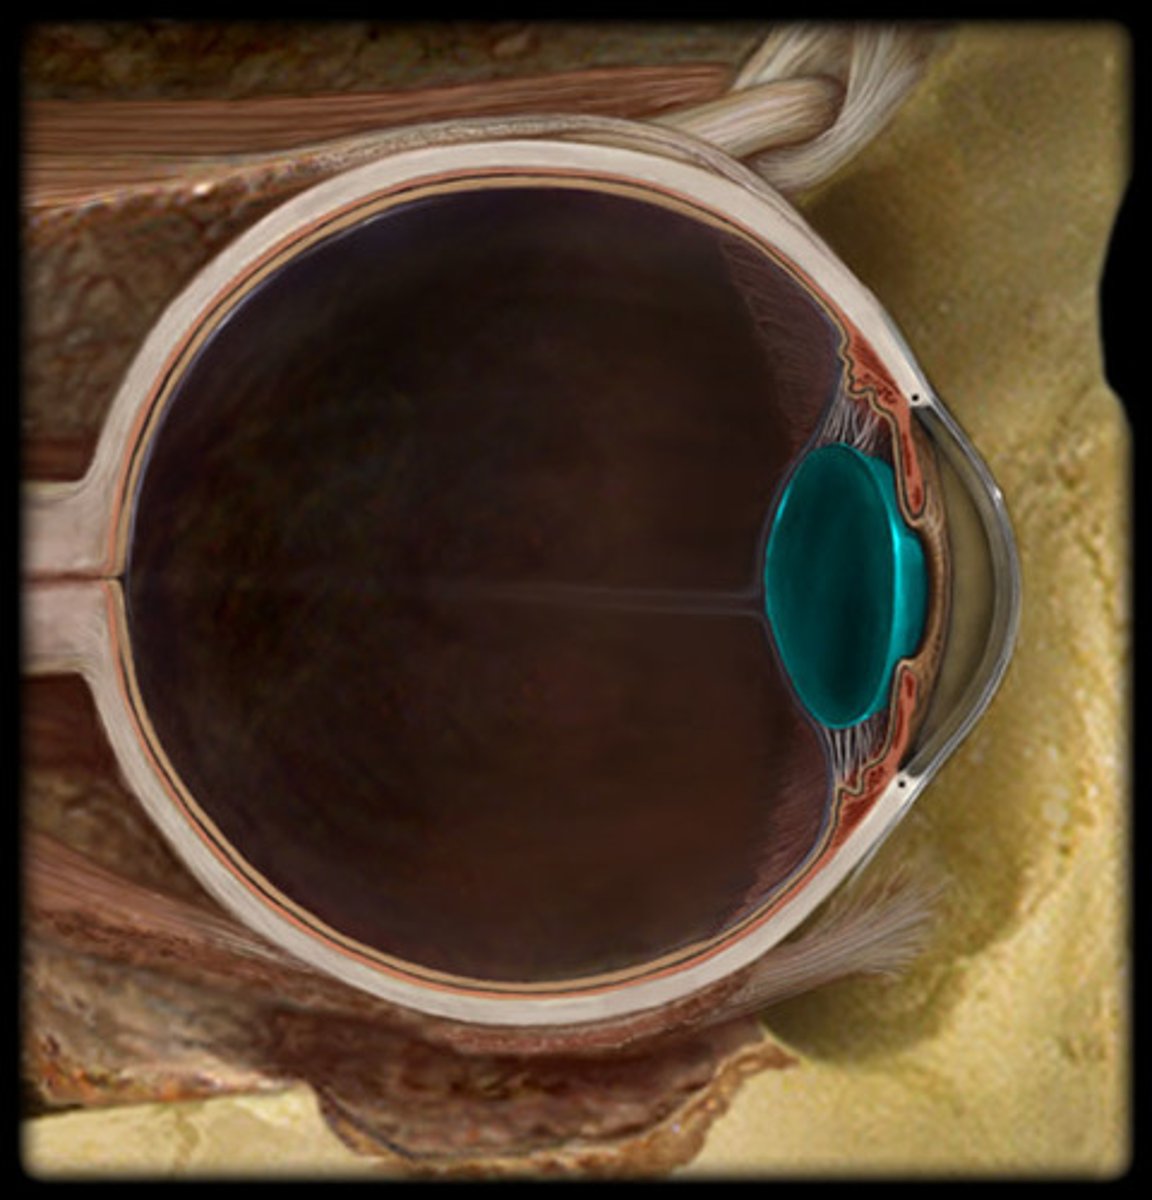

ciliary body

cornea

iris

lens

suspensory ligament of eye